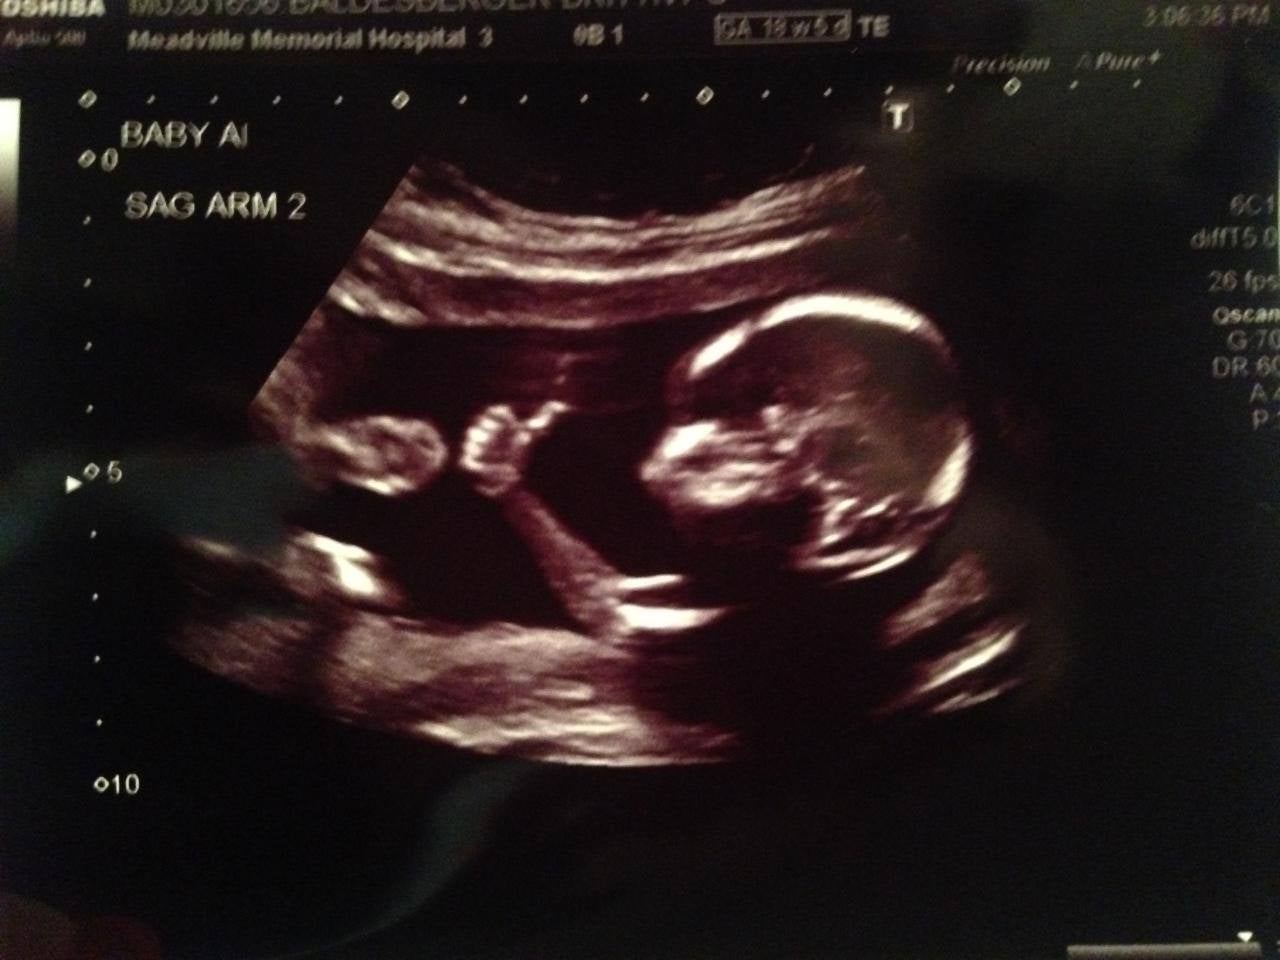

Parents delighted as baby gives thumbs up on ultrasound

'Fetus Fonzie' appeared to offer a thumbs up from the womb

It might not be a very scientific indication of how an unborn baby is doing, but it must be quite reassuring all the same when your child-to-be pops you a thumbs up on the ultrasound.

This image was posted on Reddit by user meancloth alongside the caption 'recent ultrasound result looks good', and has been viewed nearly 2 million times in 24 hours.

There was further good news too, with another user noticing the 'Baby A' on the monitor and the parent confirming that they are expecting twins.